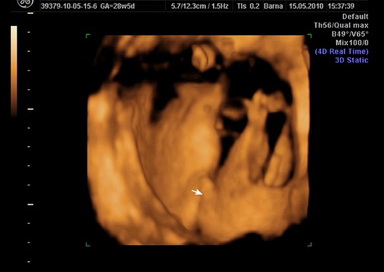

Na,más,megjártuk a Klinikát közben csak foglalt a gép,az uram nagyon maszekol. Dr Hánzli vizsgált,méh fundusa 2 harántujjal köldök felett,teljesen zárt méhszáj megtartott nyakcsatorna,magzatvíz szivárgásra utaló jel nincs. UH-ra itt átmentünk,csak ránéztek,azt mondta "van bőven vize" (???